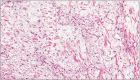

Meigs' syndrome is a benign ovarian tumor associated with ascites and pleural effusion. Elevated cancer antigen 125 (CA-125) in Meigs' syndrome is an unusual clinical condition reported in few cases. We report here on a 61-year-old woman who presented with dyspnea; in imaging assessment, a heterogeneous pelvic mass measuring 12 × 11 cm with ascitic fluid was reported. Pleural effusion was detected on Chest X-ray. Aspiration of pleural fluid showed no evidence of malignancy. CA-125 level was 347 IU/mL. The patient underwent laparotomy during which a mass measuring 12 × 11 cm was detected in her left adnexa. Histology showed ovarian thecoma. The mass was resected, and, after that, the symptoms disappeared and CA-125 level reached 19 IU/mL. The patient had experienced no problem after 12 months of follow up. Although postmenopausal women with ovarian tumor, ascites, pleural effusion, and elevation of CA-125 levels probably have malignant ovarian tumors, Meigs' syndrome must be considered in the differential diagnosis.